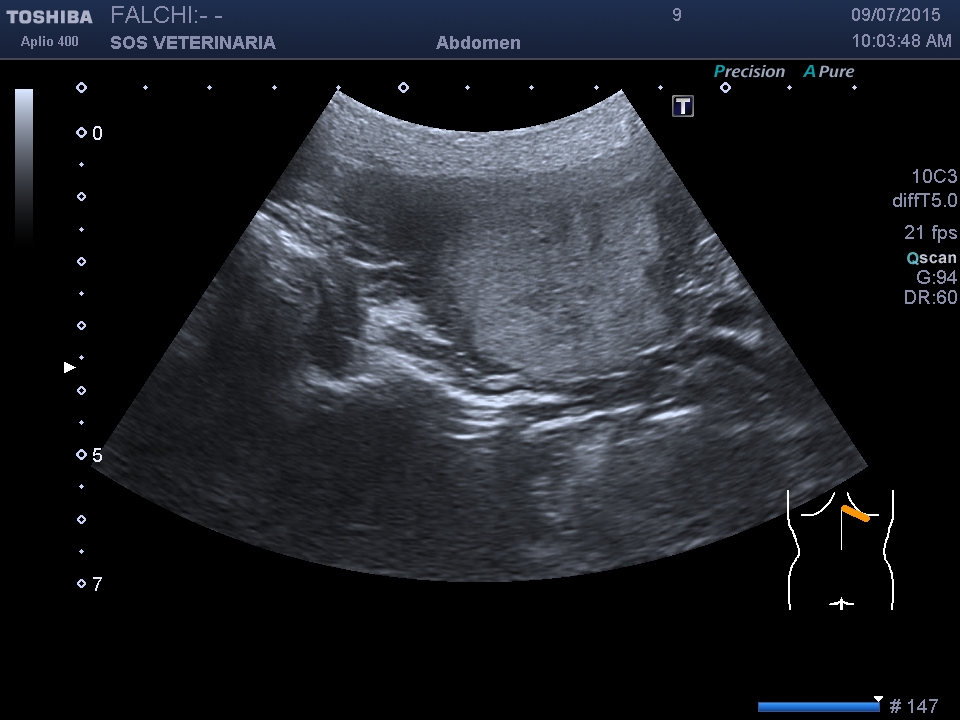

controllo dopo 4 mesi

la lesione e’ cresciuta, il cane sotto somministrazione di vetoryl e’ migliorato nei sintomi dell’ipercorticosurrenalismo ,bene sul piano generale viene visto solo per un controllo

- Nessuna informazione diversa per quello che riguarda l’esame ecografico del fegato e la presa del contrasto si confermano le lesioni individuate e l’ipoenanchement in fase portale.

la prima ecografia asse maggiore 3,5 cm

la seconda dopo 2 mesi asse maggiore 4,2 cm